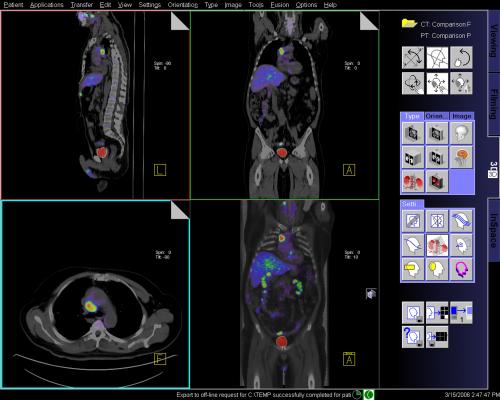

最新入荷 Imaging Features of Juvenile Xanthogranuloma of the 医学一般